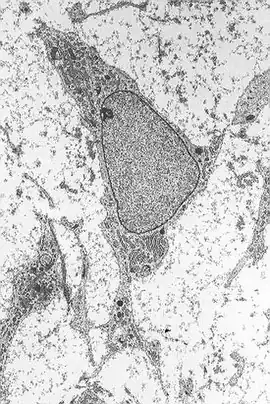

Morfologie

Het cellichaam bevat een grote, ronde celkern met een prominente nucleolus, die wordt omgeven door fijn verspreide chromatinedeeltjes, waardoor de kern een helder uiterlijk krijgt. De rest van het cellichaam bevat een kleine hoeveelheid golgicomplexen, ruw endoplasmatisch reticulum, mitochondriën en polysomen. De cellen, die lang en dun zijn, zijn wijd verspreid, en in de aangrenzende extracellulaire matrix zitten enkele reticulinevezels, maar bevat geen andere soorten collageenfibrillen. Deze onderscheidende morfologische kenmerken van mesenchymatische stamcellen kunnen ongelabeld zichtbaar worden gemaakt met behulp van time-lapse microscopy.